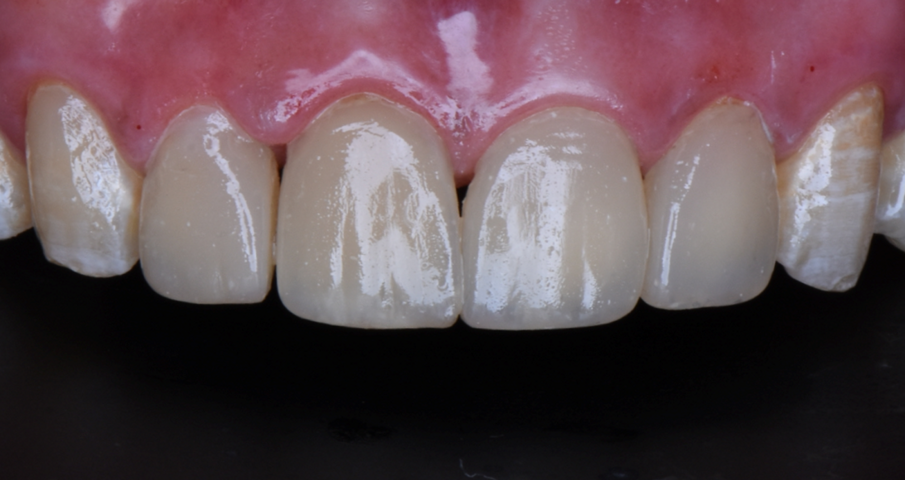

Before

After

A 44 year-old male patient came to the clinic to solve his aesthetic problem related to incisors, canines 13, 12, 11, 21, 22.

Step 8 – Post operative view Highly aesthetic outcome using (ceram.x® duo).